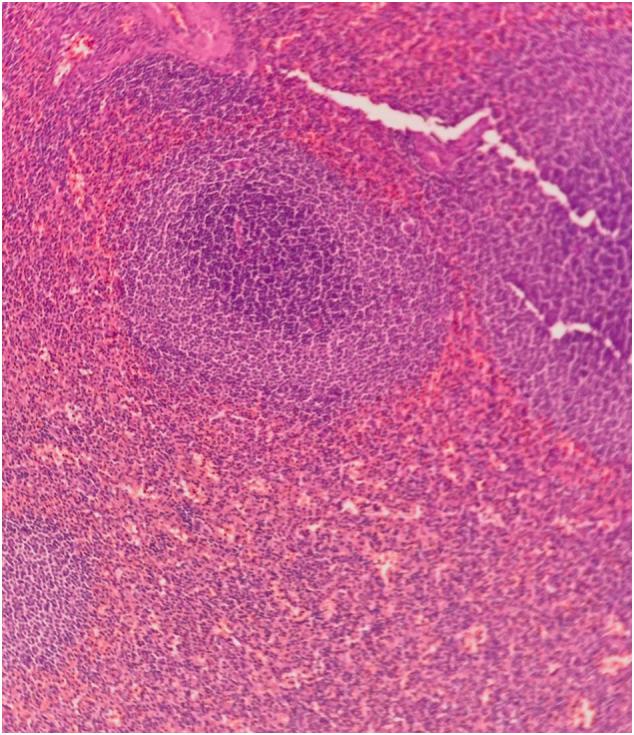

A 45-year-old female was evaluated for a 6-month history of abdominal pain in right-lower quadrant. She had past medical history of blunt abdominal trauma and splenectomy 35 years before symptoms. An abdominal contrast-enhanced computed tomography (CT) reported a 4.2 × 4.6 × 4.6 cm solid mass located in the antimesenteric border of the cecum, with calcifications and arterial enhancement. Colonoscopy found no epithelial lesions. A diagnostic laparoscopy was done, and resection of the mass achieved. Transoperative histopathological diagnosis revealed ectopic spleen tissue.

一名45岁女性因右下象限腹痛6个月接受评估。她有腹部钝性外伤史,在出现症状35年前行脾切除术。腹部增强计算机断层扫描(CT)报告在盲肠系膜对侧缘有一个4.2×4.6×4.6 cm的实性肿物,伴有钙化和动脉强化。结肠镜检查未发现上皮病变。进行了诊断性腹腔镜检查,并切除了肿物。术中组织病理学诊断显示为异位脾脏组织。